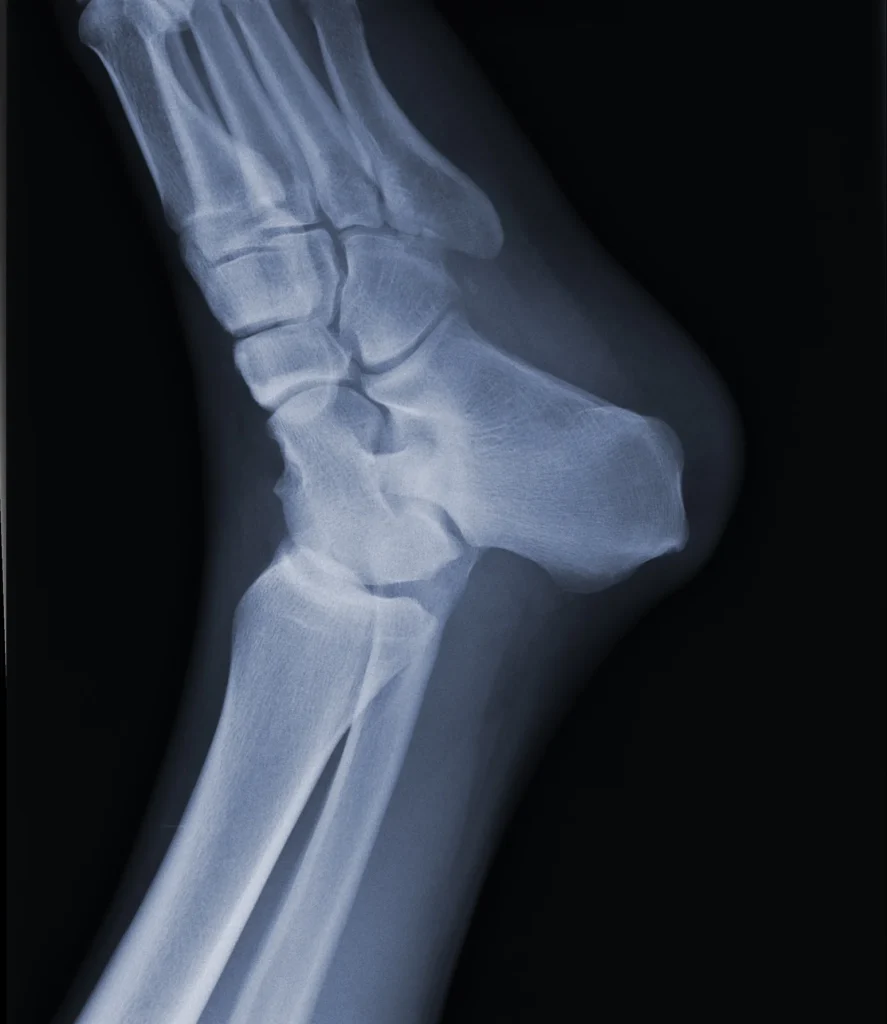

La radiografía de pie es un examen de diagnóstico por imagen que emplea rayos X para generar una representación detallada de los tejidos blandos y huesos del pie, incluyendo los huesos del tarso, metatarso y falanges.

La máquina que utiliza este examen consta de un generador de rayos X y una placa de imagen. Durante el examen, el generador emite un haz de rayos X que atraviesa el pie del paciente. Los huesos, al ser más densos, absorben más radiación y aparecen en blanco en la imagen, mientras que los tejidos blandos permiten el paso de los rayos, mostrándose en tonos más oscuros.

A través de las imágenes obtenidas con esta tecnología, es posible visualizar la presencia de fracturas en los huesos o dislocaciones en las articulaciones. En los casos en que un hueso fracturado ha sido recolocado, la radiografía se convierte en una herramienta esencial para evaluar la correcta alineación de los huesos y verificar que el proceso de curación se esté desarrollando adecuadamente.